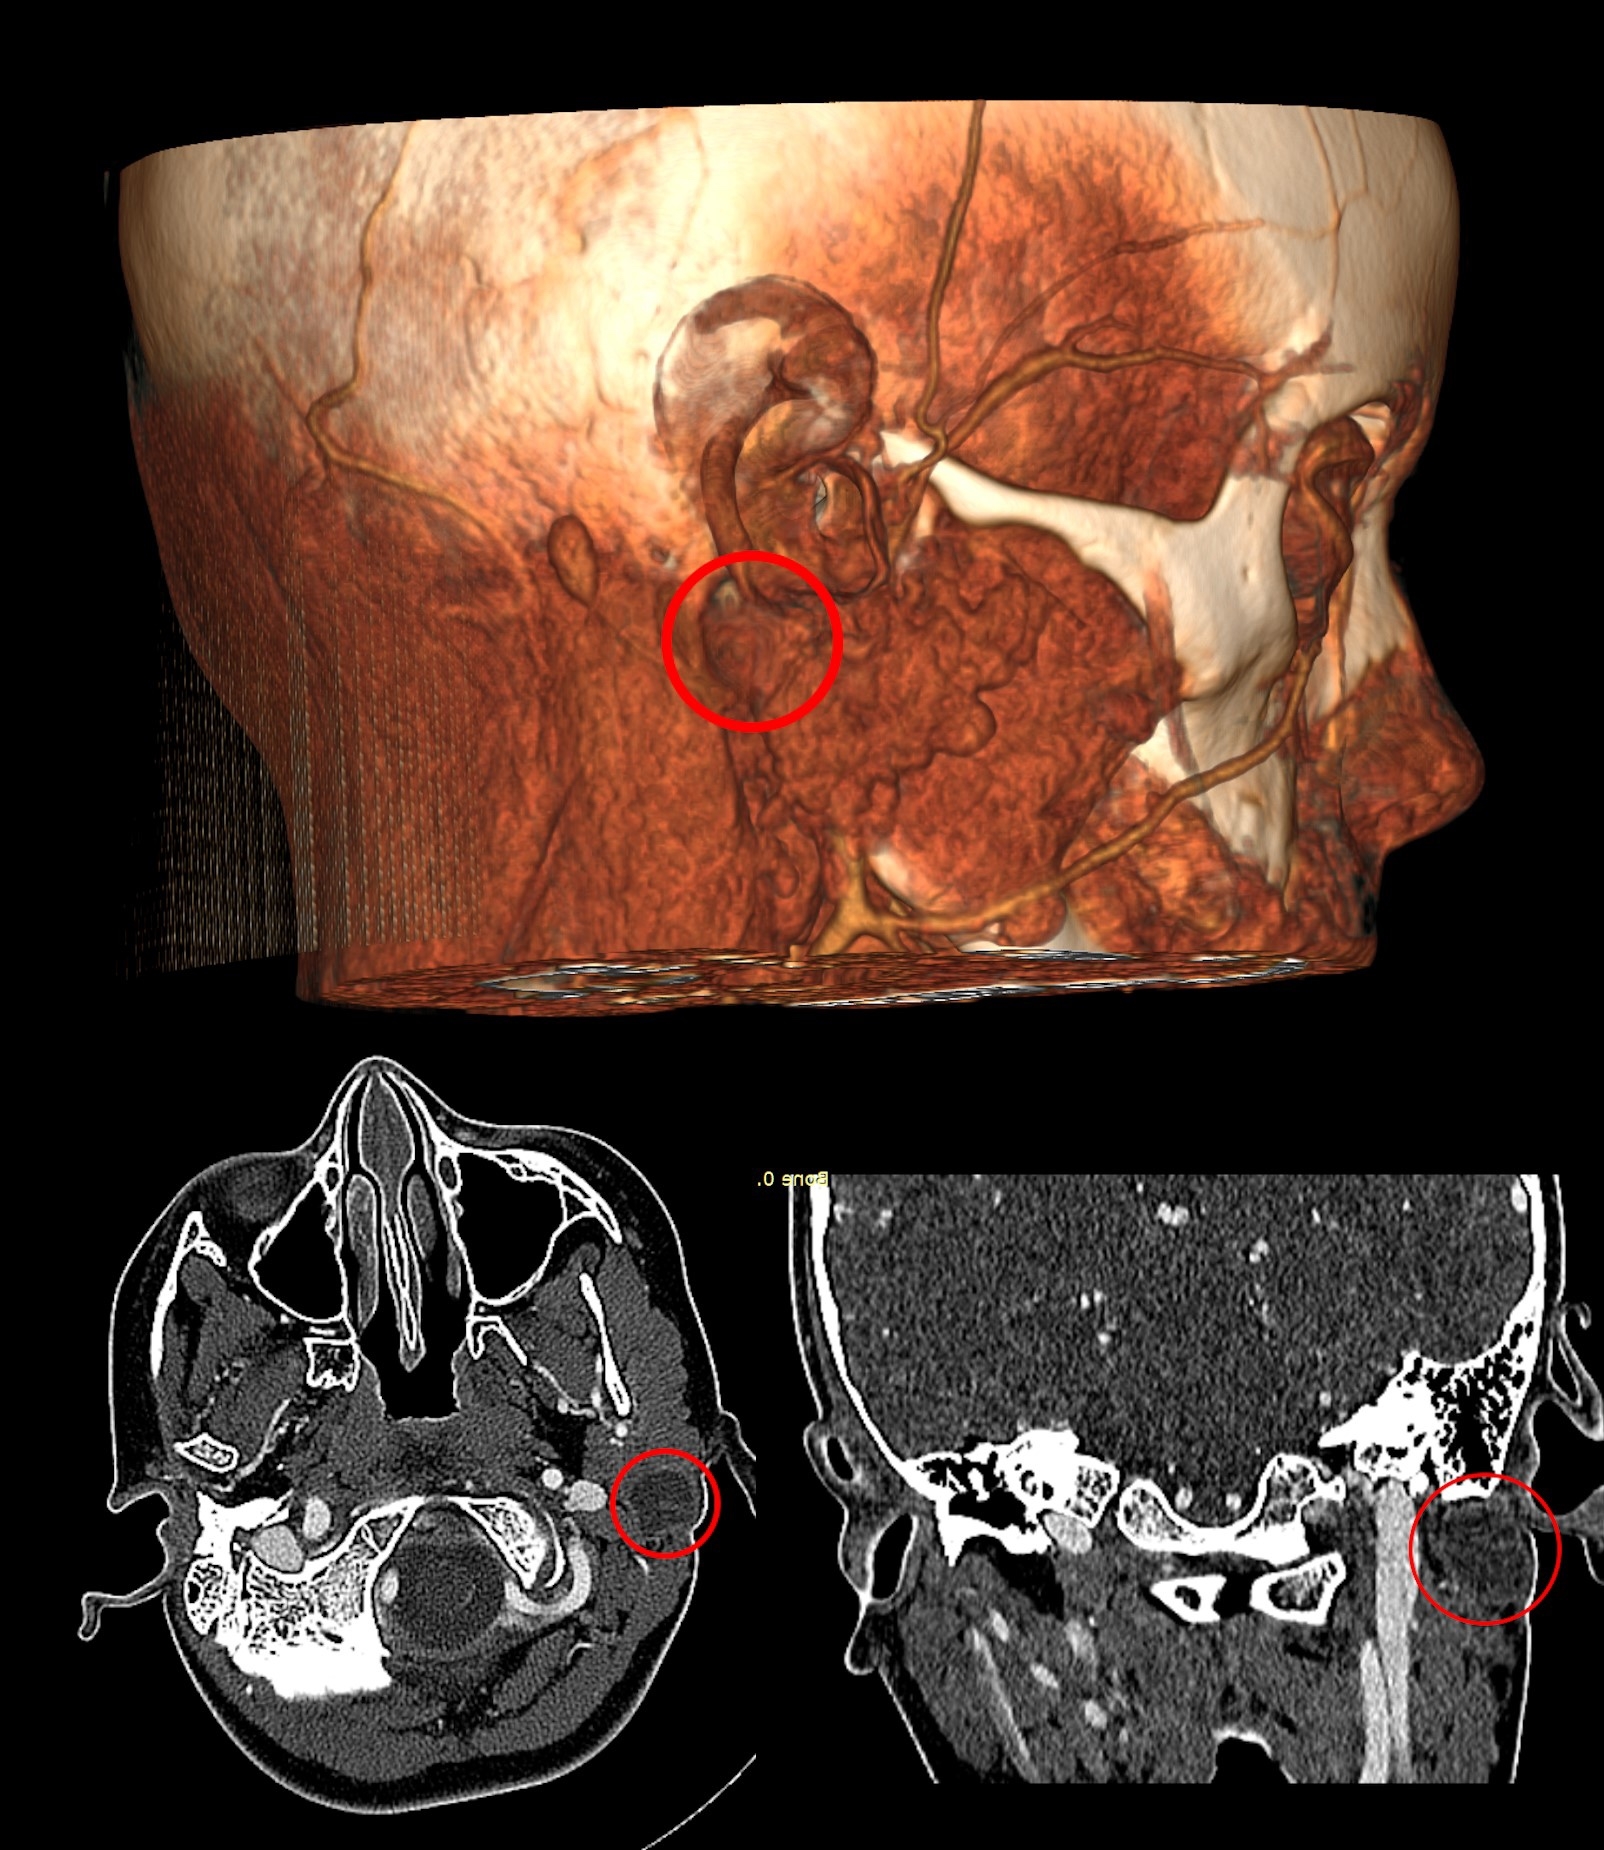

Сложность хирургического лечения заболевания обусловлена не только его редкостью, но и анатомическим расположением кисты - в глубине тканей, прилегая к жизненно важным крупным сосудам и лицевому нерву, повреждение которого грозило асимметрией лица, потерей мимики.

Как отметил Александр Кугушев, согласно мировой статистике, такие осложнения возникают у 20% пациентов, перенесших операцию при этой патологии. Несмотря на редкость заболевания и сложность его лечения, в отделении челюстно-лицевой хирургии РДКБ накоплен большой опыт оказания помощи пациентам с этими нарушениями. Благодаря этому специалистам удалось провести девочке ювелирную операцию - удалить кисту единым блоком через один небольшой разрез за ухом, избежав повреждения всех прилегающих структур.